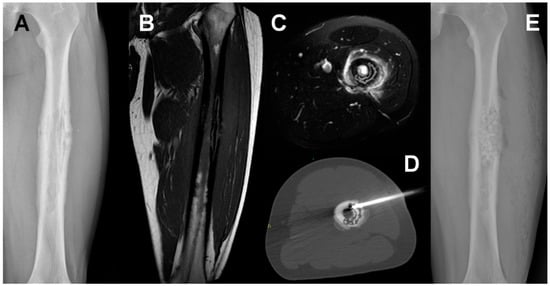

4. Chronic Osteomyelitis

- Wu, Y.; Lu, X.; Hong, J.; Lin, W.; Chen, S.; Mou, S.; Feng, G.; Yan, R.; Cheng, Z. Detection of extremity chronic traumatic osteomyelitis by machine learning based on computed-tomography images: A retrospective study. Medicine (Baltimore) 2020, 99, e19239. [Google Scholar] [CrossRef] [PubMed]

- Kaim, A.H.; Gross, T.; von Schulthess, G.K. Imaging of chronic posttraumatic osteomyelitis. Eur. Radiol. 2002, 12, 1193–1202. [Google Scholar] [CrossRef] [PubMed]